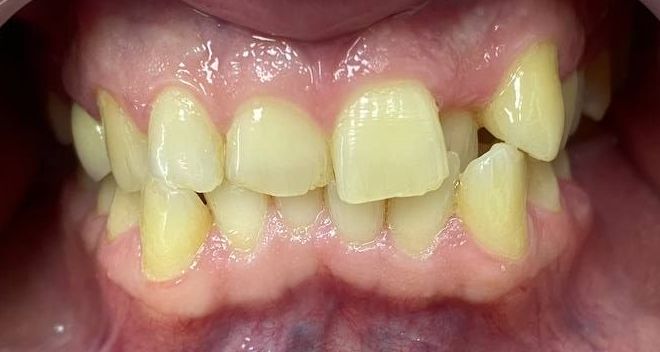

Palatal position of teeth is

characterized by the eruption of one tooth or a group of teeth outside the

dental arc on the palatal side. So, most often, incisors or second premolars

eruption.

(one or both) - 61.35%. In 57% of children, there are erased areas on the

incisal and vestibular surfaces of palatal-displaced teeth as a result of the

functional action of antagonist teeth. With a slight overlap, abrasion of the

cutting edge and shortening of the abnormally located tooth are observed. In the

palatal location of the upper jaw incisors, flattening of the frontal area of

the upper jaw and lengthening of the frontal area of the lower jaw are

determined. In this case, exposure of the necks of the lower frontal teeth,

violation of their stability and inflammation of the gums may be observed, and

the clinic of catarrhal or atrophic gingivitis develops as a result of

functional trauma.